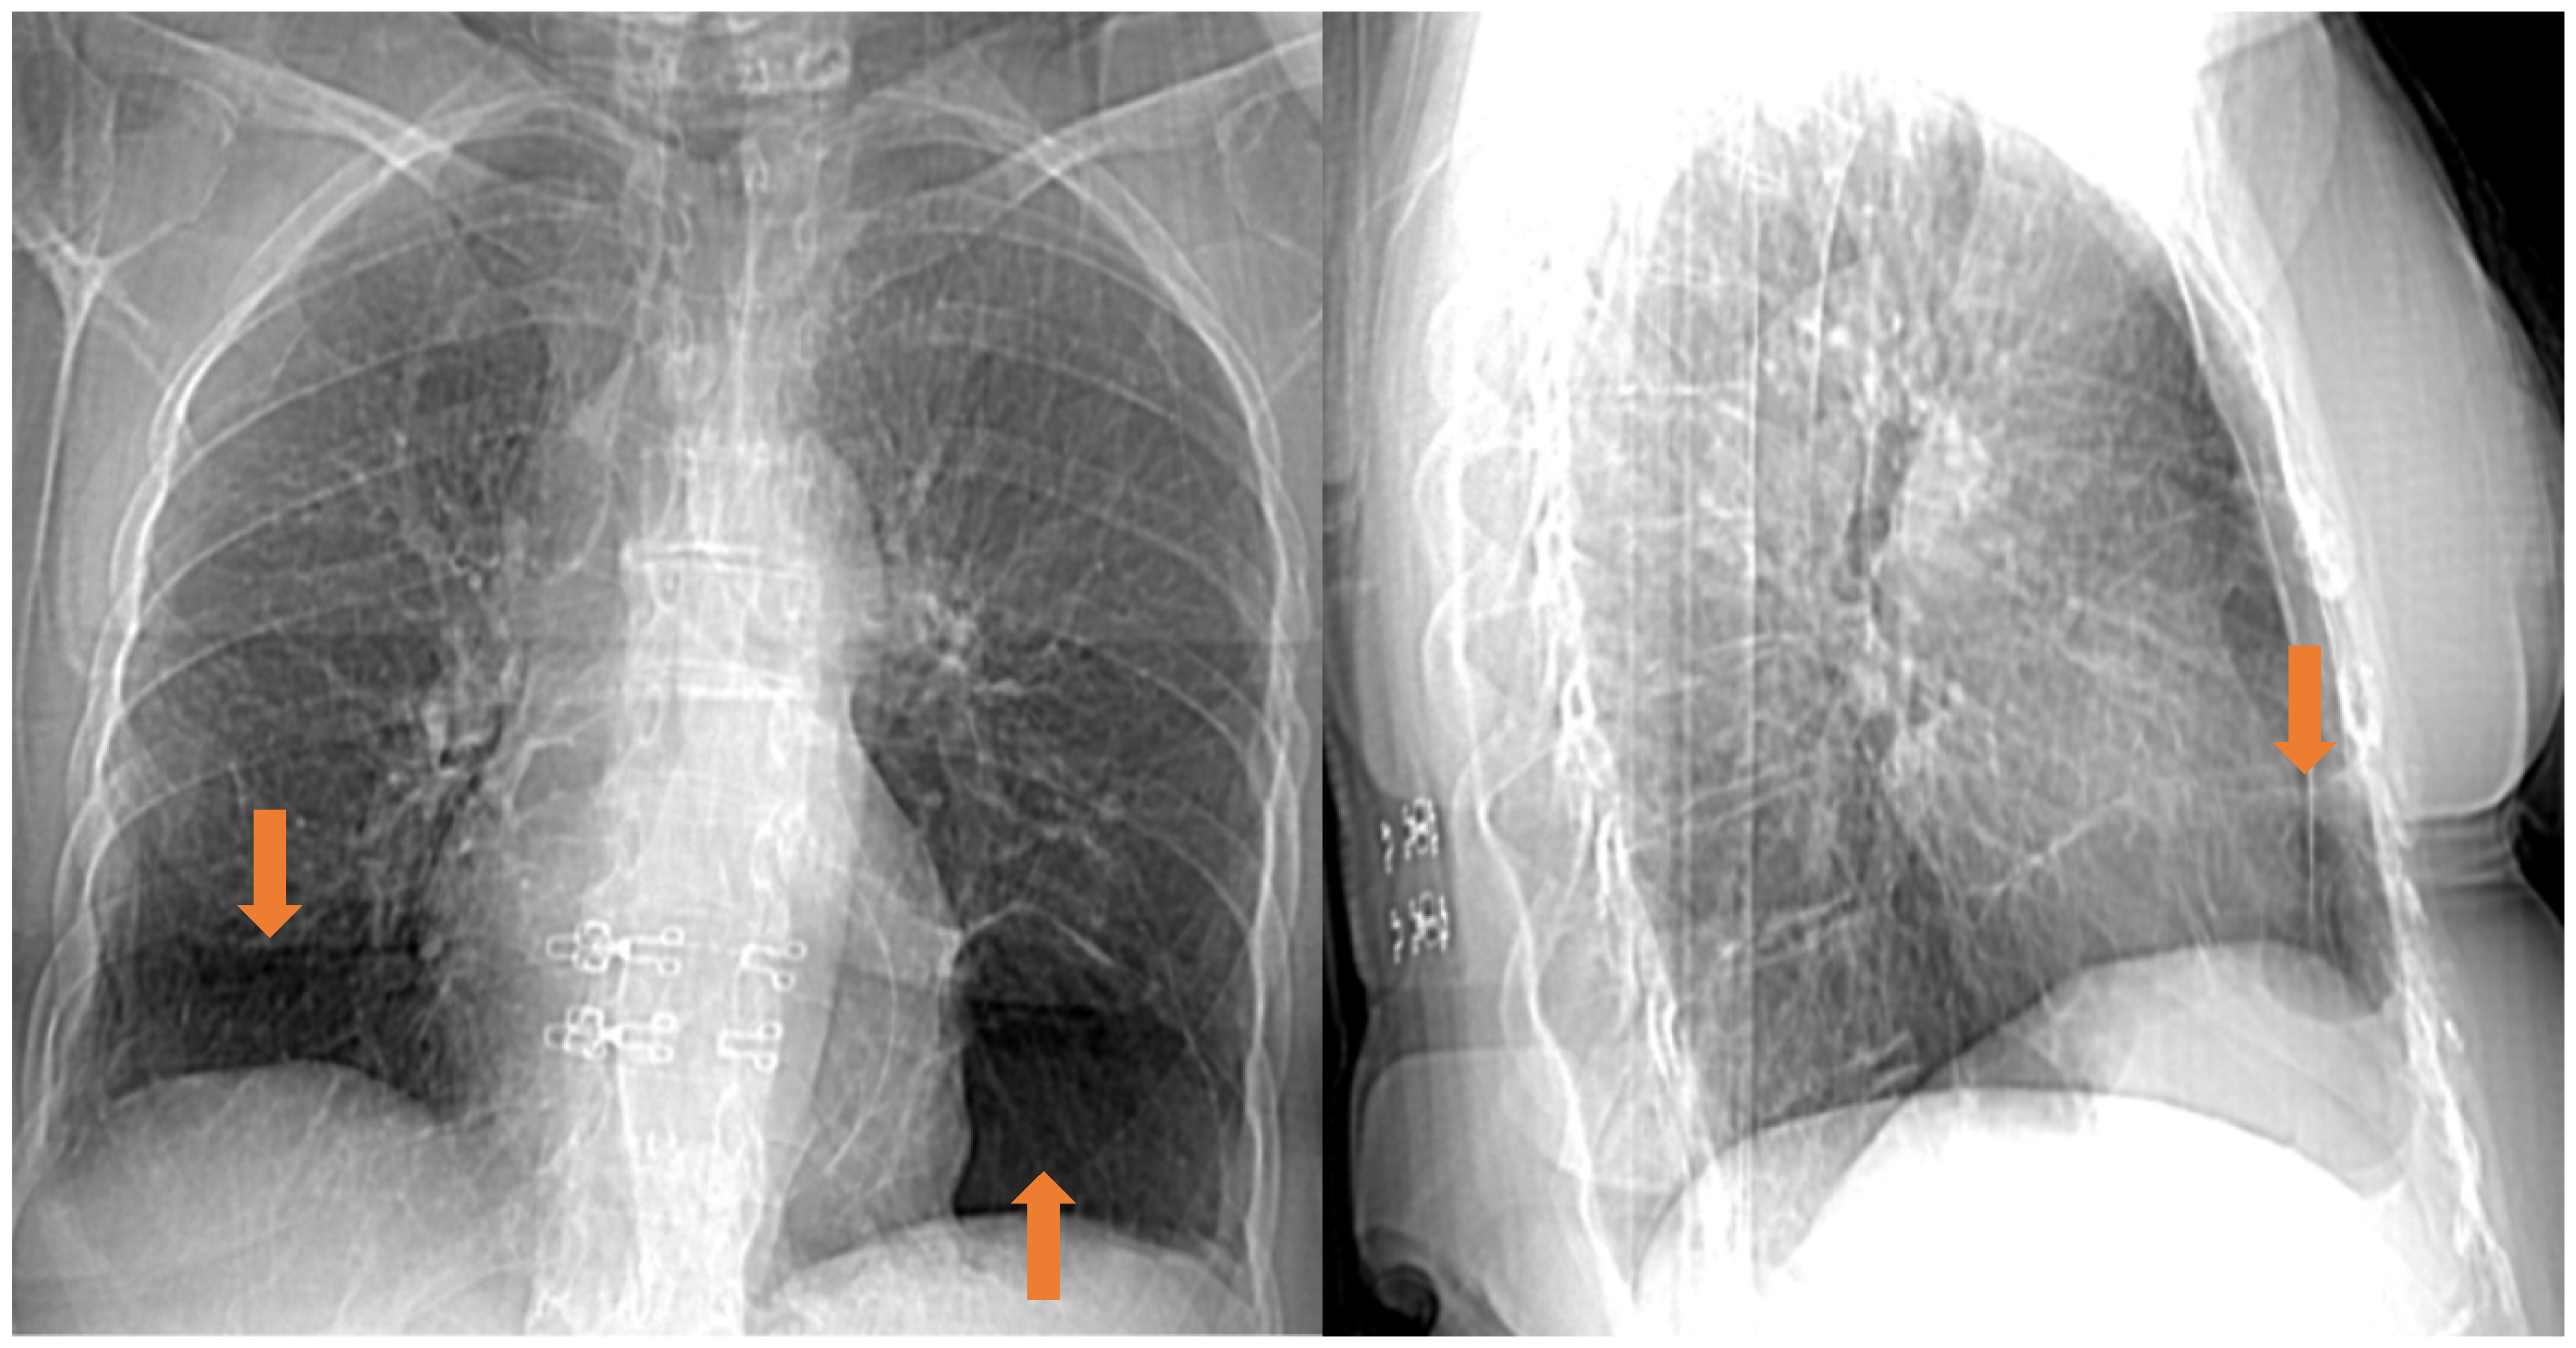

5.4. Radiological Features

- Agarwal, P.P.; Gross, B.H.; Holloway, B.J.; Seely, J.; Stark, P.; Kazerooni, E.A. Thoracic CT Findings in Birt-Hogg-Dube Syndrome. AJR Am. J. Roentgenol. 2011, 196, 349–352. [Google Scholar] [CrossRef]

- Lee, J.E.; Cha, Y.K.; Kim, J.S.; Choi, J.H. Birt-Hogg-Dubé Syndrome: Characteristic CT Findings Differentiating It from Other Diffuse Cystic Lung Diseases. Diagn. Interv. Radiol. 2017, 23, 354–359. [Google Scholar] [CrossRef] [PubMed]